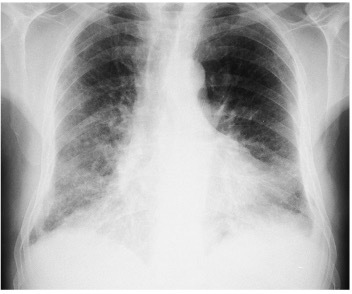

What features are seen on this CXR? What is the likely diagnosis?

Bilateral airway shadowing

Pulmonary oedema